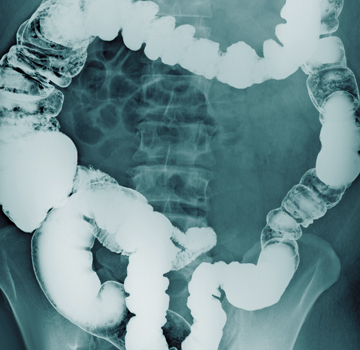

Obstrucción intestinal

Es un bloqueo que impide completamente o altera de manera importante el tránsito del contenido intestinal.

Las causas más frecuentes en adultos son el tejido cicatricial derivado de una intervención quirúrgica abdominal previa, las hernias, y los tumores.

El diagnóstico se basa en los resultados de la exploración física y radiológica.

Síntomas: Dolor abdominal severo, vómitos, inflamación, gases fuertes, hinchazón del vientre, incapacidad para eliminar gases, estreñimiento, Para su tratamiento con frecuencia.